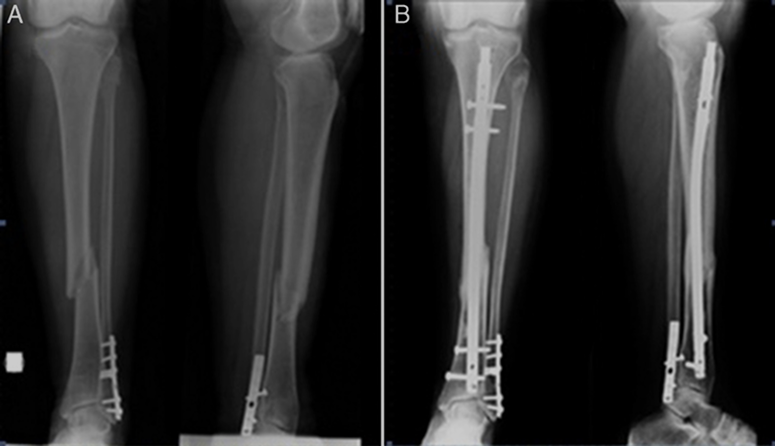

- Fracturas con desplazamiento: Generalmente requieren cirugía para alinear los huesos mediante el uso de clavos o placas metálicas.